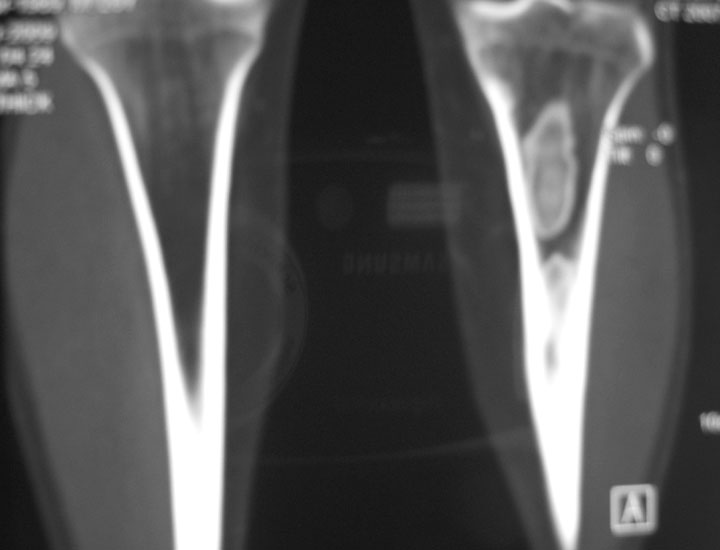

标题: CT19885:左胫骨上端肿瘤。 [打印本页]

标题: CT19885:左胫骨上端肿瘤。

男,20岁,医学院学生,11年前感左胫骨上端劳累后酸痛,曾由父母带到国内好几家有名望的医院诊治,但众说不一,所以基本上没有治疗。今年三月又开始出现症状,又到多家省级医院求治,但专家们的意见还是不能统一。各生化检查正常。mri考虑到胫骨上端良性血管瘤可能性大。ct考虑纤维瘤可能性大。请各位发表高见。